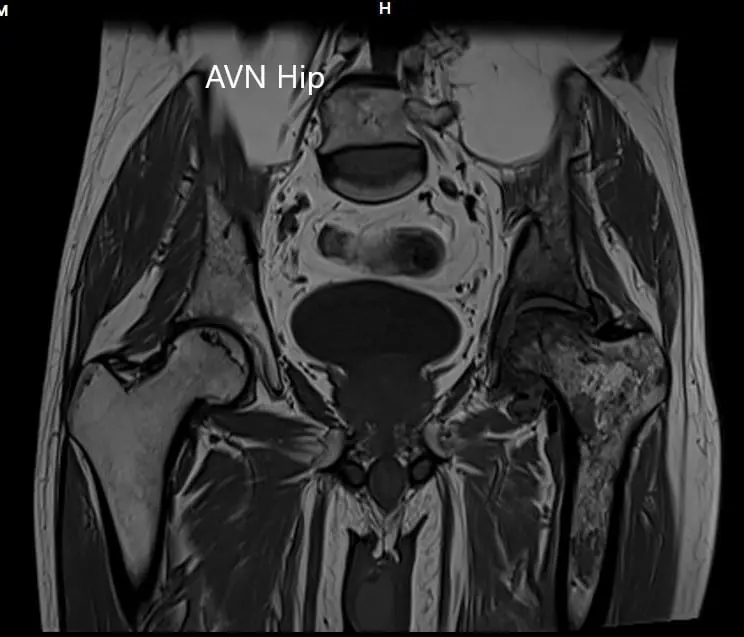

An MRI of the pelvis was obtained which suggested decreased signal intensity on both T1WI and T2WI suggesting sclerosis and periarticular edema. There was a collapse of the head of the femur. The features were suggestive of advanced avascular necrosis of the left hip joint.

MRI showing the T2WI of the pelvis

CMRI showing the T2WI of the pelvis